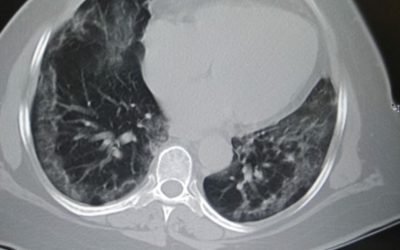

How to deal with post-Covid Lung Fibrosis?

Originally posted 21st Aug 2020; Updated: 1st Sept. 2020. Q: What is the protocol for residual lung dysfunction post Covid19 which is very common in patients who have suffered lung affection to the tune of 30 percent or more? CME INDIA Discussion: Dr Raju Sharma,...